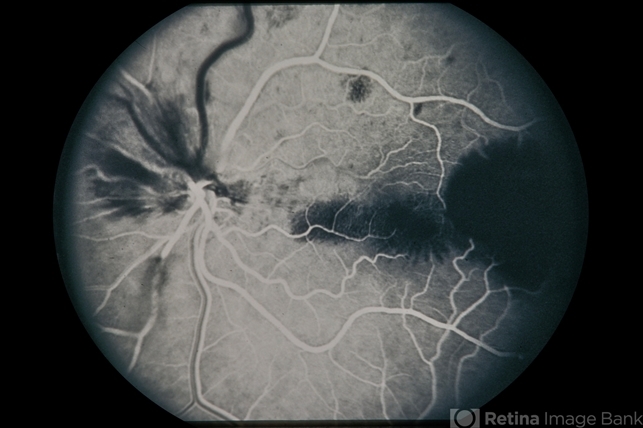

Pre-Retinal and Intra Heme from Trauma

PreRetinal and Intra Heme from Trauma

trauma, hemorrhage

43-year-old white female, pre-retinal and intra heme from trauma.